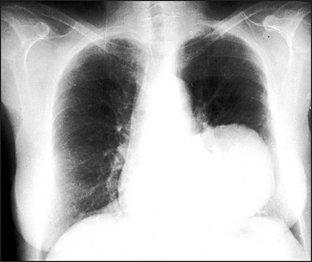

Figure 12.10 Pulmonary metastases Multiple rounded opacities are seen in both lung fields, mainly at the left base and around the right hilum. The most likely cause is multiple pulmonary metastases. Other rare possibilities are hydatid cysts, large sarcoid nodules or large rheumatoid nodules. Multiple abscesses are extremely unlikely in the absence of cavitation.